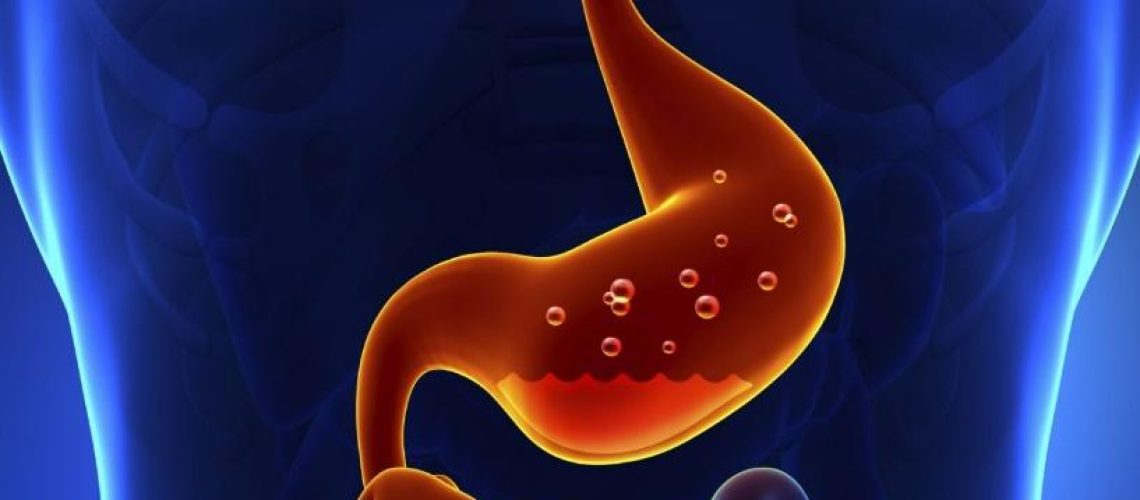

سوء هاضمه یا دیس پپسی به مجموعهای از علائم ناراحتکننده در ناحیه بالایی شکم اطلاق میشود که معمولاً پس از خوردن غذا تجربه میشود. این وضعیت شامل احساس ناراحتی، درد، سنگینی، سوزش یا بادگلو در ناحیه معده است. سوء هاضمه ممکن است به طور موقت یا مداوم رخ دهد و میتواند کیفیت زندگی فرد را به شدت تحت تأثیر قرار دهد.

این وضعیت ممکن است ناشی از عوامل مختلفی مانند خوردن غذاهای سنگین، استرس، مصرف داروها یا مشکلات گوارشی باشد. در برخی موارد، سوء هاضمه میتواند نشانهای از مشکلات جدیتر مانند زخم معده یا بیماری رفلاکس معده به مری باشد. در نتیجه، تشخیص و درمان مناسب این مشکل از اهمیت ویژهای برخوردار است.

علائم سوء هاضمه میتوانند به شکلهای مختلفی ظاهر شوند و شامل احساس ناراحتی یا درد در ناحیه بالای شکم، احساس سنگینی یا پر بودن بعد از غذا خوردن، سوزش سردل، تهوع و بادگلو میشوند. این علائم ممکن است به طور موقت یا مداوم باشند و میتوانند با شدتهای مختلفی تجربه شوند.

در برخی موارد، علائم میتوانند به حدی شدید باشند که فعالیتهای روزانه فرد را مختل کنند. همچنین، سوء هاضمه ممکن است باعث کاهش اشتها و احساس سیری زودهنگام شود. در صورت وجود علائمی مانند کاهش وزن غیرعمدی، استفراغ مکرر، مشکلات بلع یا مدفوع سیاه، نیاز به مشاوره فوری با پزشک وجود دارد، زیرا این علائم میتوانند نشانههایی از مشکلات جدیتر باشند.